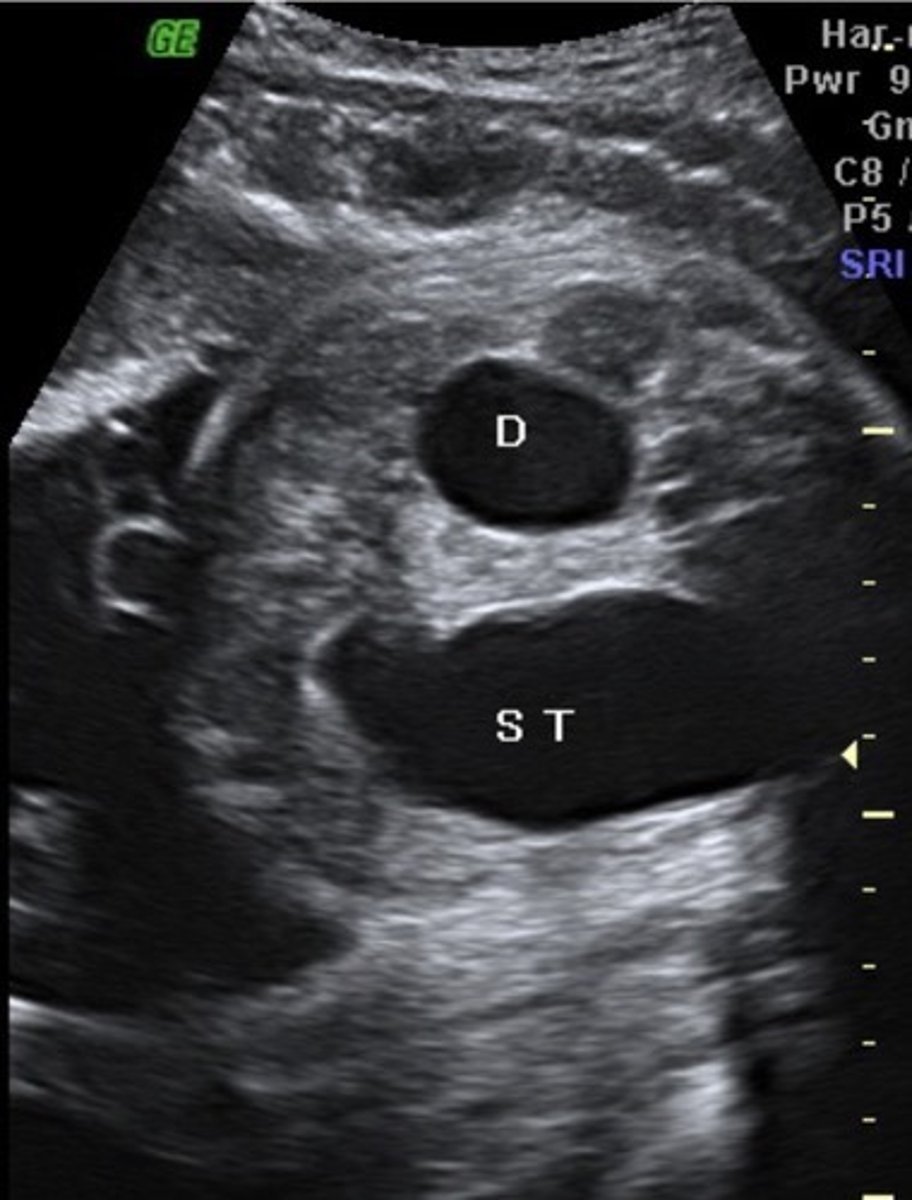

Duodenal Atresia

Fluid reaches duodenum, but cannot move past it

Double Bubble Sign

Enlarged stomach & prox. duodenum